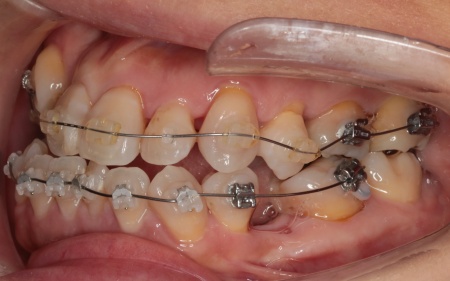

治療前

診断結果 拝見したところ、上下の歯がデコボコに乱れて生えていました。

歯の大きさに対して顎が小さいため、歯が正常に並びきらず、全体的な噛み合わせのバランスも崩れています。

噛み合わせを詳しく検査したところ、実際にしっかりと噛み合っているのは一部の歯だけで、このまま放置すると特定の歯に負担が集中し、将来的に痛みや違和感が生じるおそれがあります。

また、銀歯が装着されている右下奥歯は以前神経を抜く治療がされていましたが、現在は歯の具合が良好とはいえず、温存が難しい状態です。